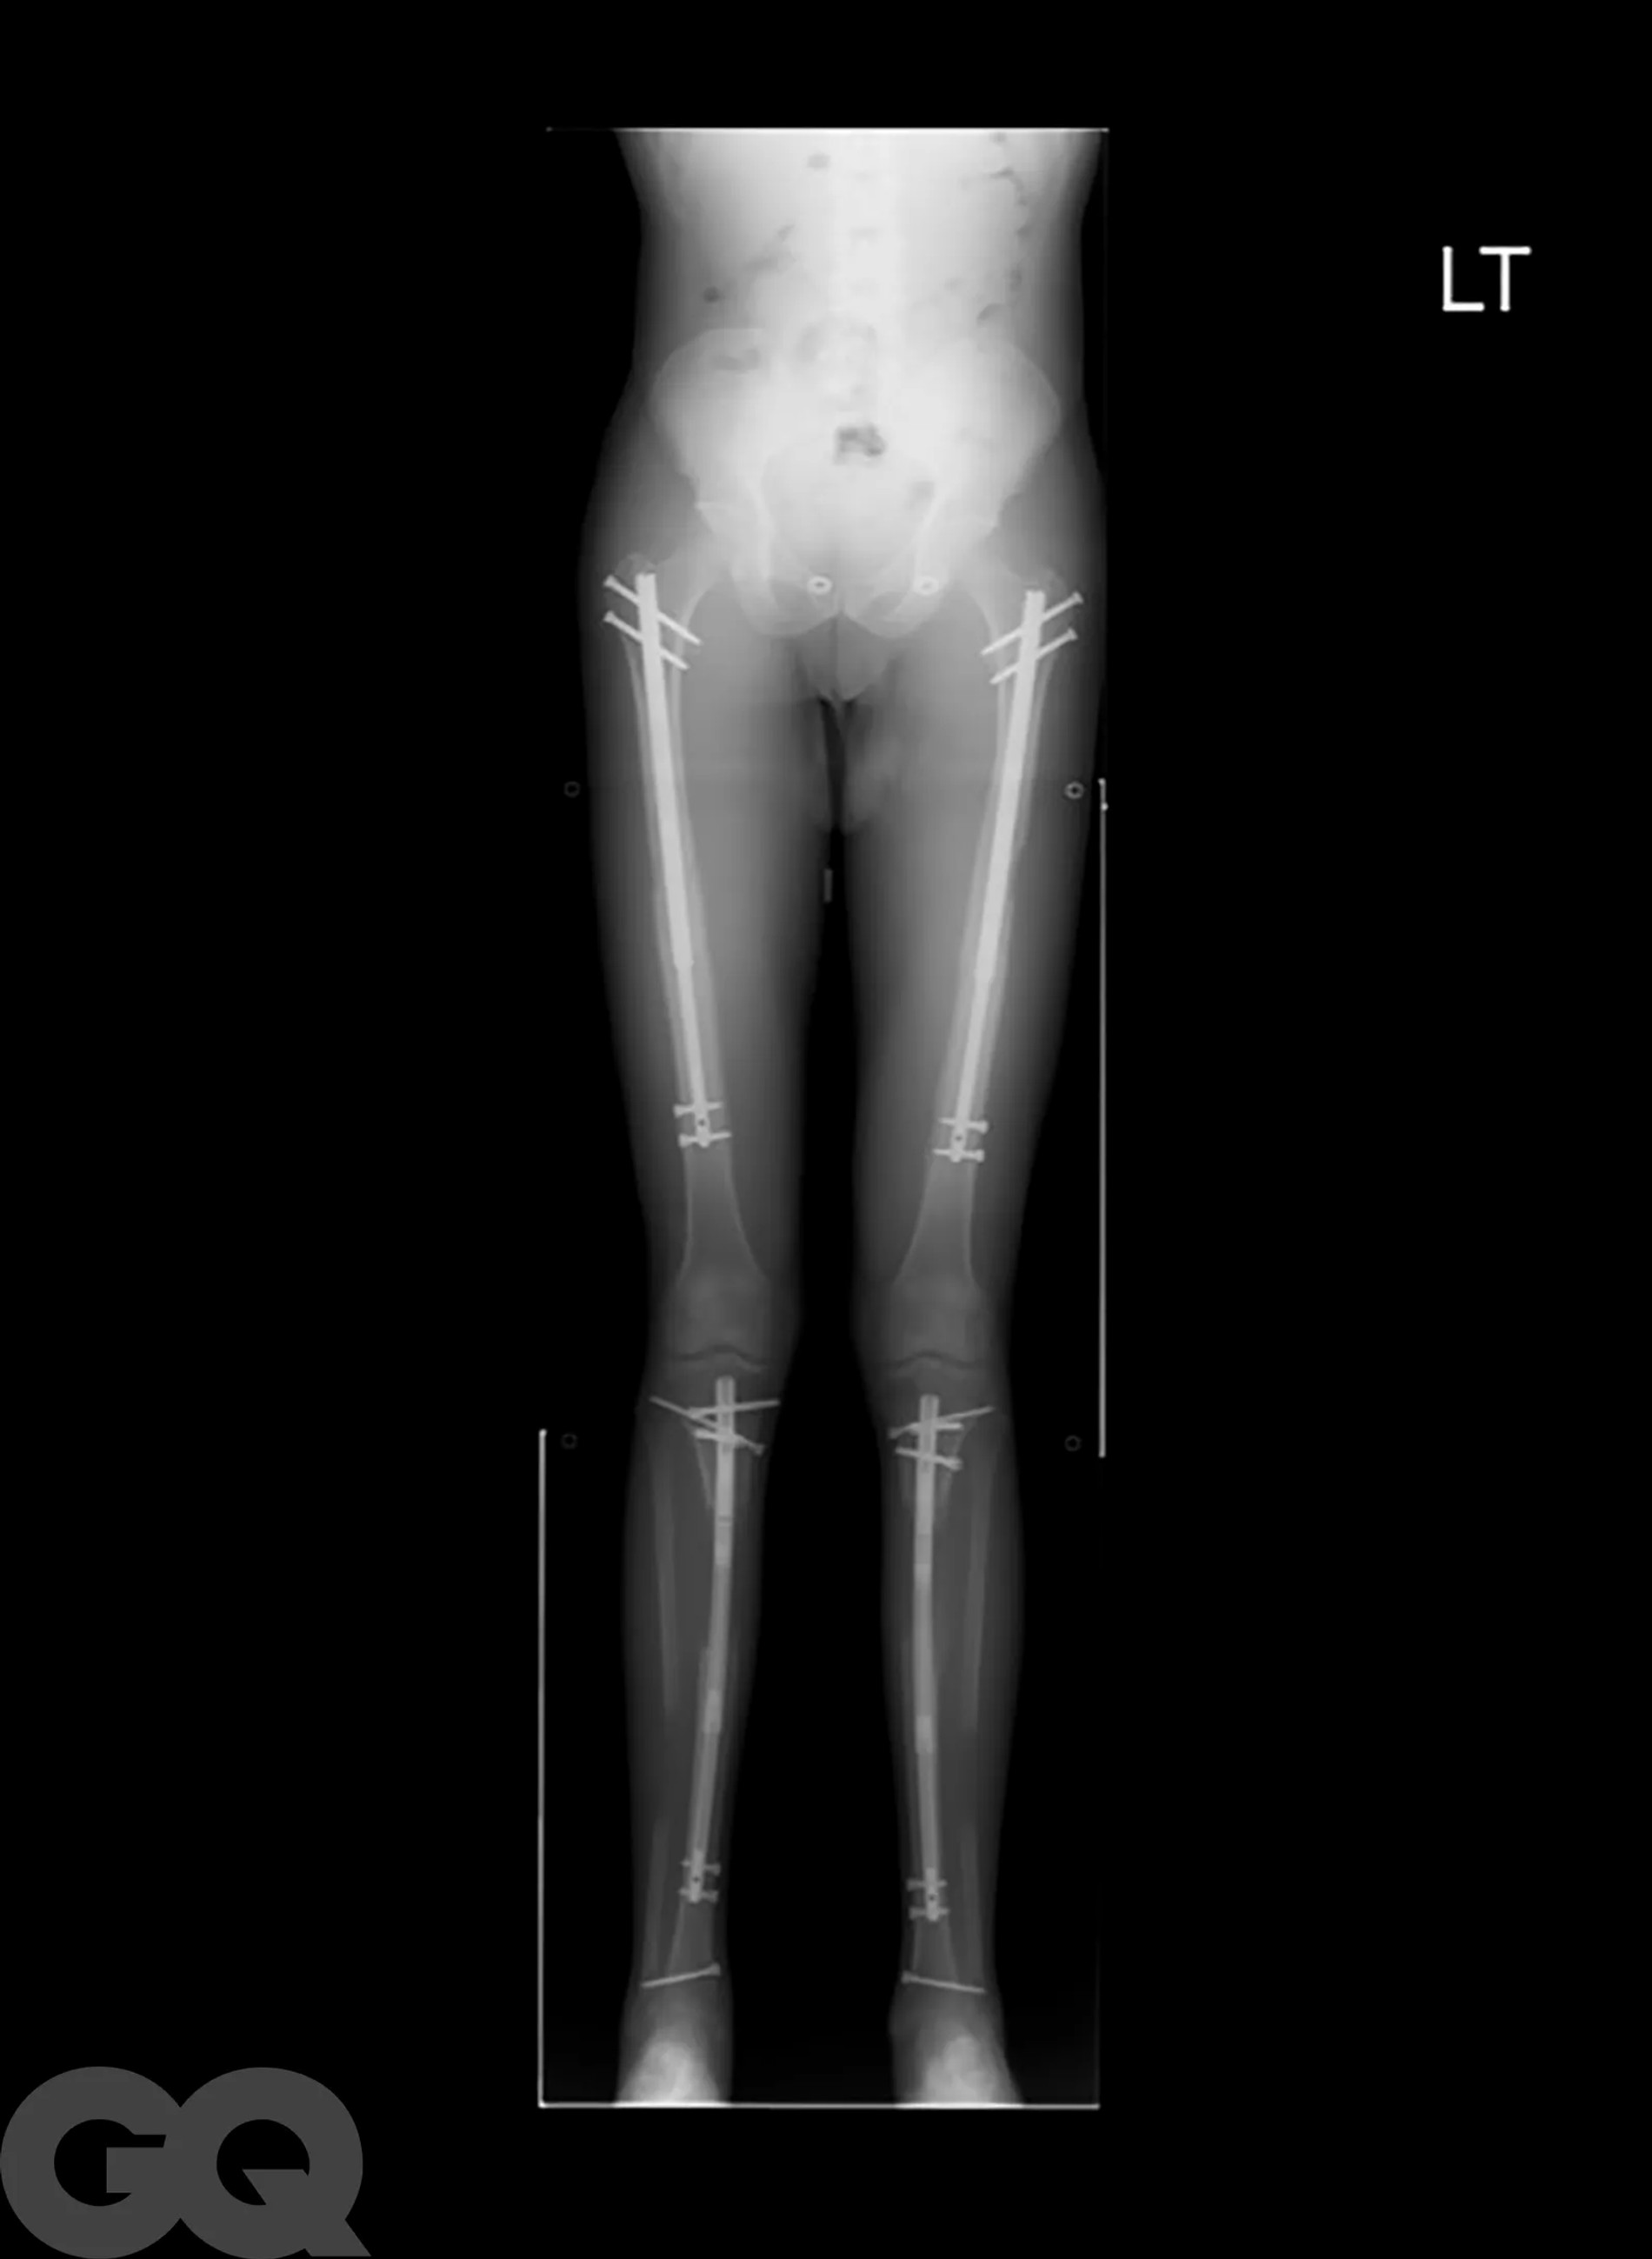

Надо сказать, что операция эта больше напоминает самую настоящую экзекуцию. Она основана на методике советского хирурга-ортопеда Гавриила Илизарова, которая изначально была разработана для пациентов со сложными переломами костей. Американские специалисты ее доработали и сделали более щадящей, но все же. В погоне за несколькими добавочными сантиметрами мужчины соглашаются на то, чтобы их собственные бедренные кости были сломаны. Да, без этого никак.

После перелома между костями вставляют регулируемые титановые стержни, которые наращивают на один миллиметр каждый день в течение примерно 90 суток с помощью магнитного пульта дистанционного управления. Как только сломанные кости срастутся, человек становится выше ростом и снова может ходить. Обычно весь процесс занимает 1 год, реабилитация сопровождается болью, что нисколько не смущает мужчин, решивших немного подрасти.